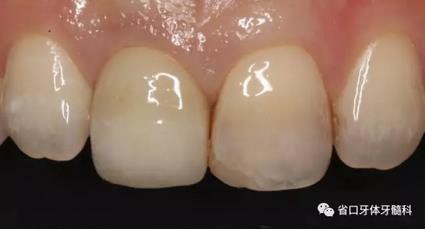

圖33 就位全瓷冠

圖34 負(fù)重3個(gè)月后

圖35 負(fù)重6個(gè)月后復(fù)診

上頜右側(cè)中切牙修復(fù)體固位良好,牙齦乳頭充盈良好,齦緣水平對稱 修復(fù)體與對側(cè)同名牙協(xié)調(diào)一致。外觀笑容美觀協(xié)調(diào)?;颊邼M意。X線檢查示 上頜右側(cè)中切牙種植體周穩(wěn)定骨質(zhì)包繞,唇側(cè)骨板>2mm,相鄰牙槽骨高度穩(wěn)定,基臺(tái)及修復(fù)體就位良好。分別根據(jù)Furhauser的PES和Bulser的WES 進(jìn)行美學(xué)評分,總分值為20,美學(xué)效果良好。